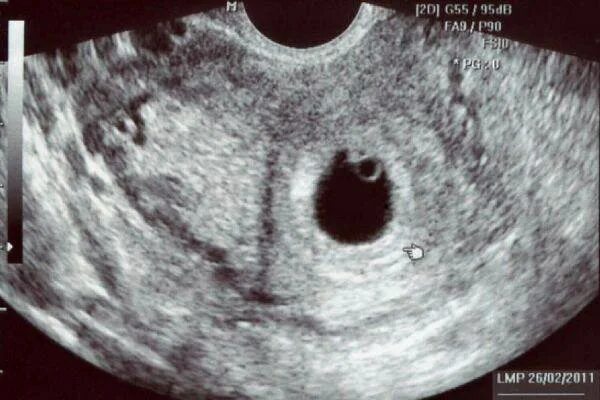

Через 4 6 недель после